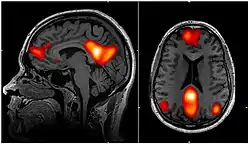

fMRI scan showing regions of the default mode network; the dorsal medial prefrontal cortex, the posterior cingulate cortex, the precuneus and the angular gyrus | |

In neuroscience, the default mode network (DMN), also known as the default network, default state network, or anatomically the medial frontoparietal network (M-FPN), is a large-scale brain network primarily composed of the dorsal medial prefrontal cortex, posterior cingulate cortex, precuneus and angular gyrus. It is best known for being active when a person is not focused on the outside world and the brain is at wakeful rest, such as during daydreaming and mind-wandering. It can also be active during detailed thoughts related to external task performance.[3] Other times that the DMN is active include when the individual is thinking about others, thinking about themselves, remembering the past, and planning for the future.[4][5]